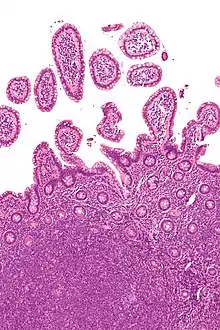

Histology of a normal lymphoid follicle, with yellow arrows pointing at mantle zone.

Lymph node with mantle cell lymphoma (low power view, H&E)

Mantle cell lymphoma. Notice the irregular nuclear contours of the medium-sized lymphoma cells and the presence of a pink histiocyte. By immunohistochemistry the lymphoma cells expressed CD20, CD5 and cyclin D1 (high power view, H&E)